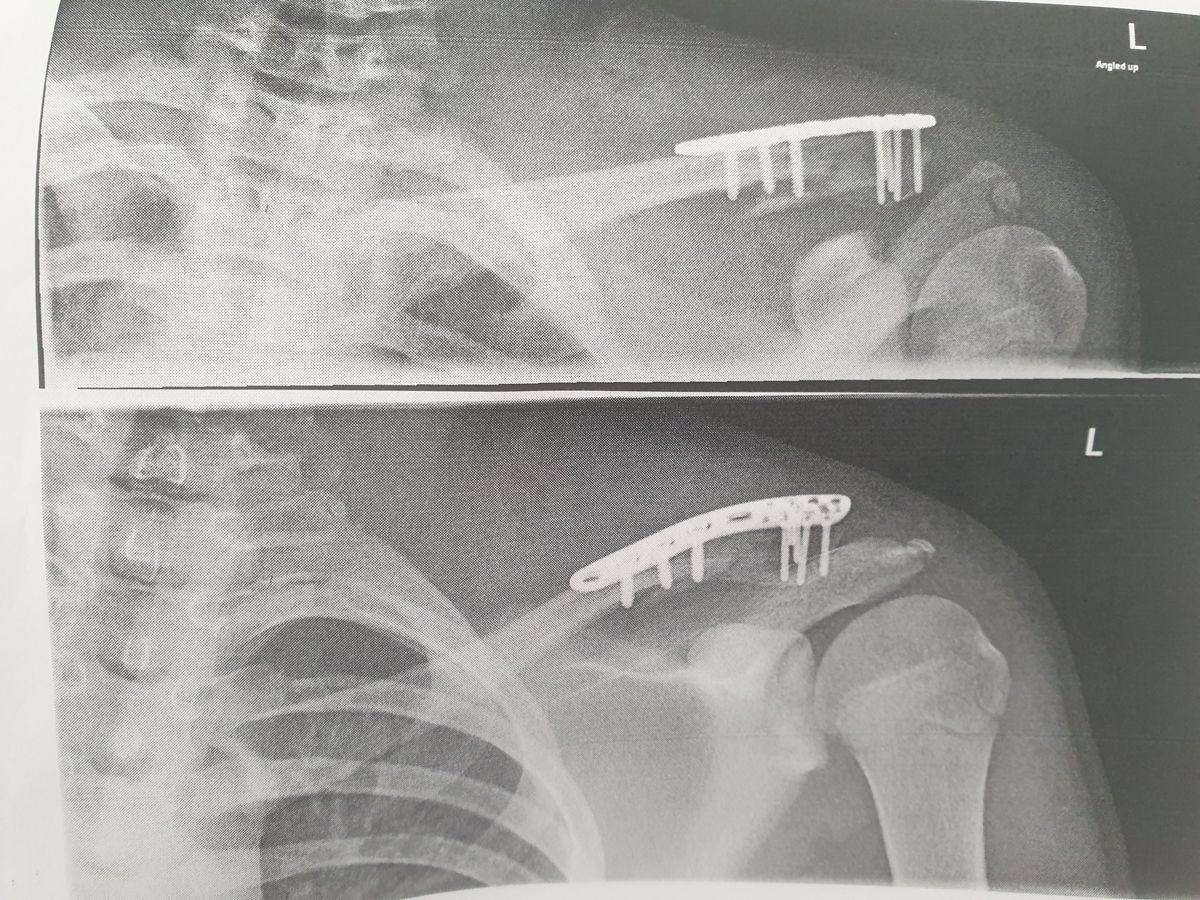

Taken to Brighton's Royal Alexandra Children's Hospital, an x-ray revealed that Tom had broken his collarbone on the left side and had a hematoma – a swelling where blood collects outside the blood vessels – because a small piece of bone had penetrated his muscle.

Sent home with a sling and painkillers, he returned to hospital two days later for an operation to insert a metal plate into his shoulder and retrieve the piece of bone that had pierced his muscle.

With the metal plate, it can take three to four months to heal and Tom has been told to avoid anything that risks shattering the bone – meaning he could not ride his bike, swim or play sports throughout the summer vacation.